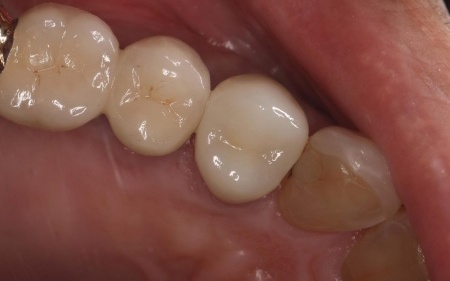

60代男性 歯に合わなくなった被せ物をジルコニアクラウンに交換した症例

拝見したところ、右上4番目の歯には白い被せ物が入っていましたが、加齢により歯ぐきが下がったことで被せ物が合わなくなり、土台が見えて黒くなっていました。

この歯は笑ったときに見えやすい部分のため審美性に影響が出ており、さらにこのまま放置すると隙間から細菌が入り込んで虫歯が再発するリスクもあります。

患者様は「見た目がきれいで長持ちする被せ物がいい」と希望され、被せ物の種類は自由診療のセラミックであるジルコニアクラウンを選択しています。

その後、周りの歯と色調や形を合わせた被せ物を作製・装着し、見た目や噛み合わせに問題がないことを確認して治療を終了しました。